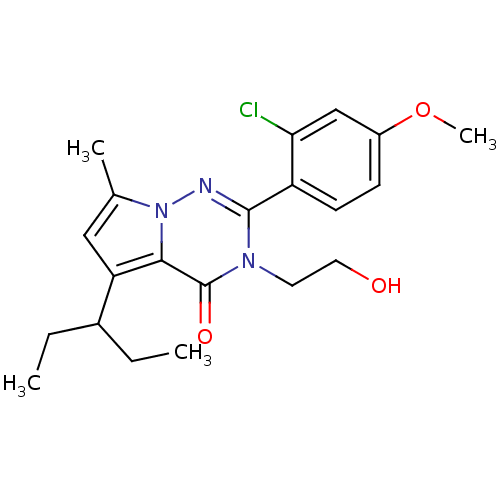

TargetCorticotropin-releasing factor receptor 1(Homo sapiens (Human))

Dupont Pharmaceuticals

Curated by ChEMBL

Dupont Pharmaceuticals

Curated by ChEMBL

Affinity DataEC50: 0.600nMAssay Description:Antagonist activity at human CRF1 receptor expressed in CHO-K1 cells assessed as CRF-stimulated cAMP accumulation by enzyme immunoassayMore data for this Ligand-Target Pair